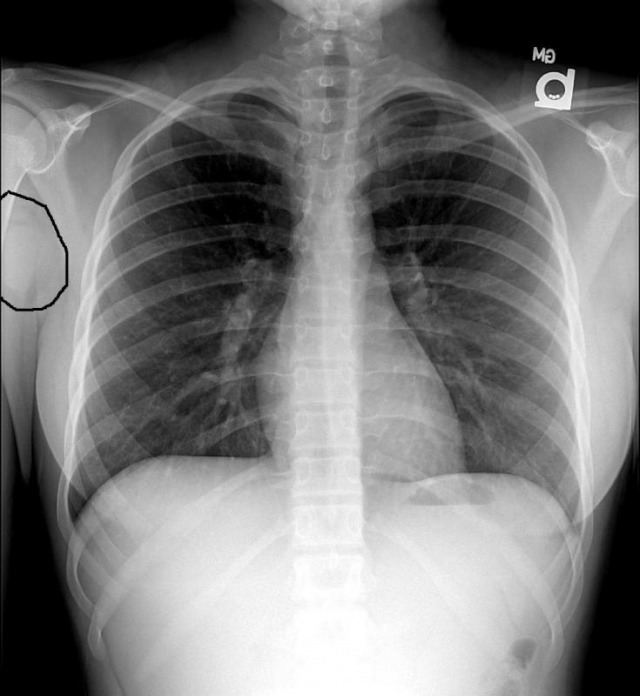

1. What is the key finding.

The key finding is, as encircled in this image, a rounded opacity in the right axilla. Here are select CT images demonstrating the presence of several opacities in the right axillary region. The opacities represent lymphadenopathy. Compare with the left axilla where there is no evidence of enlarged lymph nodes.

Diagnosis: Hodgkin's lymphoma (biopsy confirmed). The patient has stage I disease, in other words the disease was limited to a single lymph node group in the right axilla. No additional disease was found in the head, neck, chest, abdomen, or pelvis on CT examination. Clinical examination failed to demonstrate lymphadenopathy in other sites in the appendicular skeleton.